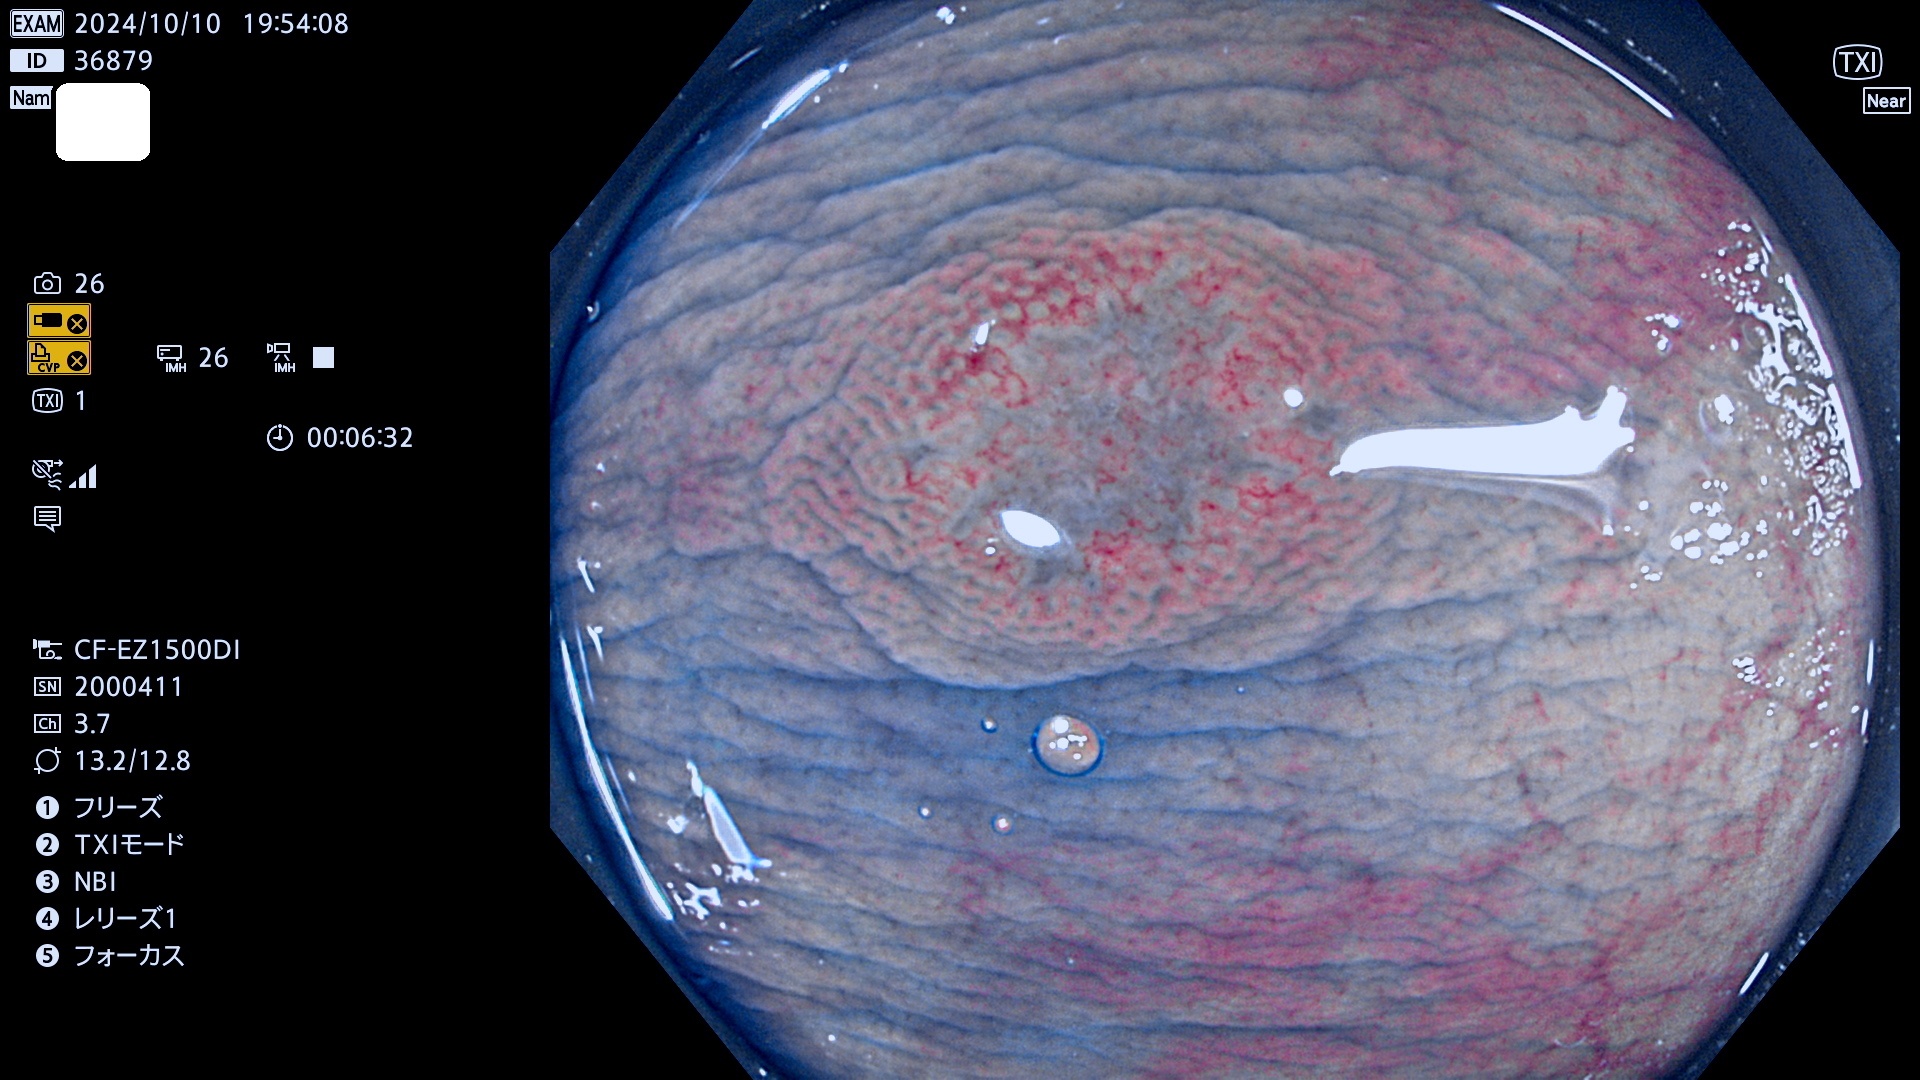

今週のUb、Uc型腺腫

完全に平坦な物をUb、陥凹している物をUcと呼びます。最も発見が難しく危険な病変です。

毎週の検査(木・金・土・日)に発見されたUb、Uc型・腺腫を、その週の日曜の夜にUPし1週間、提示します。

抽出の対象期間 2024年10月10日〜10月13日の4日間(48件の検査)7件 (7/48=14%)